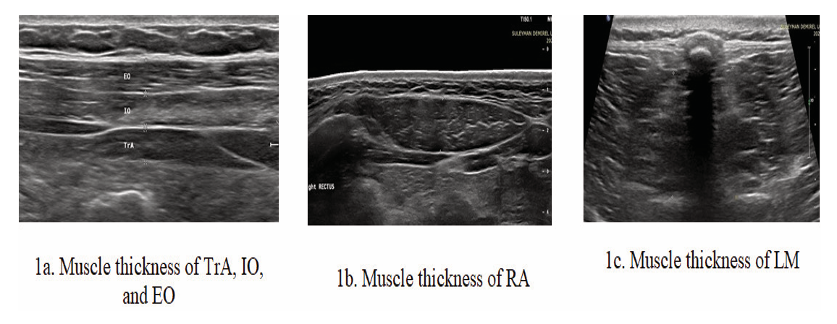

Transversus Abdominis and Internal and External Oblique: The measurement was made by positioning the probe on the midline between the anterior axillary line, where the middle fibers of TrA and OI can be viewed simultaneously, and the iliac crest and lower rib (Figure1a), [9].

Rectus Abdominis Muscle: The probe was placed 3 cm lateral to the umbilicus, and the measurement was taken at rest (Figure 1b), [10].

Lumbar Multifidus Muscle: With the patient positioned in the prone position, the probe was placed longitudinally in the midline of the L4 spinal process. Then, it was moved slightly laterally and angled medially to obtain an image of the L4-5 zygapophysis joint (Figure 1c), [11].

Figure 1. 1a. Muscle thickness of transversus abdominis and internal and external oblique, 1b. Muscle thickness of rectus abdominis, 1c. Muscle thickness of lumbar multifidus